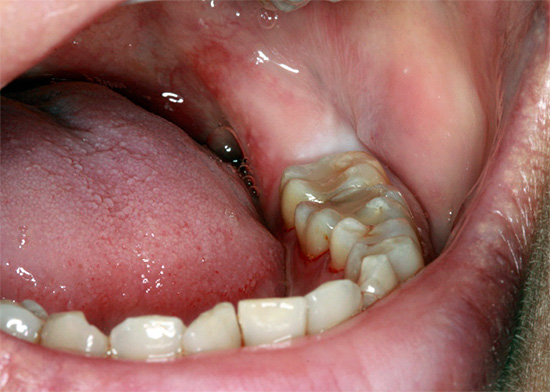

La foto sotto mostra le fasi iniziali della procedura per la rimozione del dente del giudizio retinirovannogo (cioè nascosto sotto la gomma):